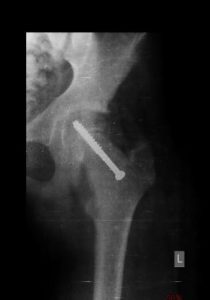

The goal of treatment is to prevent the femoral head from further slippage. This usually needs surgery which may be:

* Fixing a metal screw to prevent the femoral head from slipping further.

* Putting the slipped ball back into previous position and then fixing it with screw.